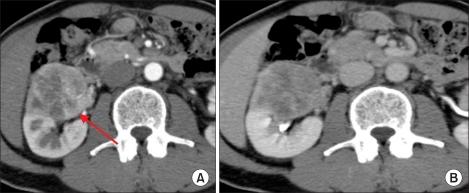

A 63-year-old male patient visited our hospital with a right incidental renal tumor, which was found by ultrasonography for the follow-up study of chronic hepatitis B virus infection and diabetes mellitus. Consecutive computed tomography revealed a right renal tumor and two left adrenal tumors. Further systemic imaging study and hormonal examination suggested one right renal cell carcinoma and left adrenal metastases. We performed right nephrectomy and left adrenalectomy. The pathological diagnoses of all resected tumors were renal cell carcinoma. The patient has been in good health without any recurrence for 12 months since the operation. In patients with renal cell carcinoma, contralateral adrenal metastasis is usually associated with multiple metastases to other organs. There are a few cases of solitary and synchronous contralateral adrenal metastasis in the English literature. To our knowledge, this is the first report of a case of renal cell carcinoma with double synchronous contralateral adrenal metastases.

一名63岁男性患者因右肾偶然发现的肿瘤前来我院就诊,该肿瘤是在对慢性乙型肝炎病毒感染和糖尿病进行超声随访检查时发现的。连续的计算机断层扫描显示右肾有一个肿瘤以及两个左肾上腺肿瘤。进一步的全身影像学检查和激素检查提示为右肾细胞癌伴左肾上腺转移。我们实施了右肾切除术和左肾上腺切除术。所有切除肿瘤的病理诊断均为肾细胞癌。自手术以来,患者已健康存活12个月,无任何复发迹象。在肾细胞癌患者中,对侧肾上腺转移通常与其他器官的多发转移相关。英文文献中仅有少数孤立性和同步性对侧肾上腺转移的病例报道。据我们所知,这是首例双发性同步对侧肾上腺转移肾细胞癌病例的报告。